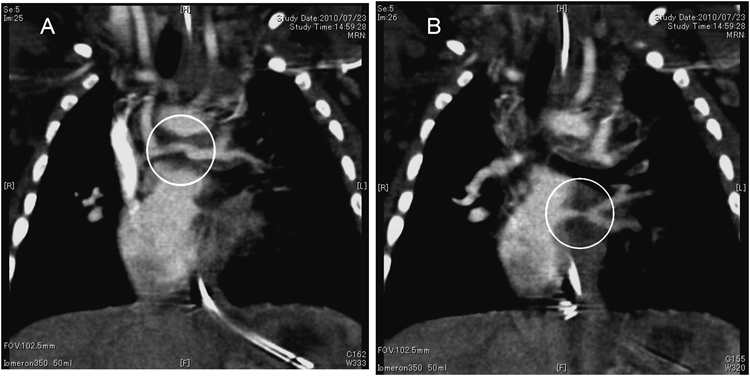

生後146日,左側方開胸でアプローチし,左BTシャント変法(3.5 mmφ)を行った.生後157日に撮影したMDCTでは左共通肺静脈は細いものの肺内PVの拡張を認めた(Fig. 3).生後163日(体重3,357 g)にPVO解除を行った.胸骨再正中切開,血液温21°Cで大動脈遮断して循環停止にした.右側心房を切開して肺静脈の入口部を観察した.右肺静脈の入口部には内膜の肥厚はなく,狭窄を認めなかった.左肺静脈入口部は肥厚し狭小化していた.鉗子を挿入し,注意深く内腔を確認しながら壁に切開を加えた.最も狭い部分を越えて瘢痕組織を全周性に切除すると,左肺静脈の内膜が外れ,瘢痕組織の腔を介して左上下肺静脈が観察された(Fig. 4).瘢痕組織のみのSuturelessとした.人工心肺の離脱に問題なく閉胸して手術を終了した.体外循環時間:116分,大動脈遮断時間:26分,循環停止時間:20分であった.術翌日に抜管し,抜管直後からSpO2は80%(room air)を示すようになった.その後の経過は良好で,生後245日(体重3,466 g)で自宅退院となった.1歳3ヵ月の心臓カテーテル検査では,右肺動脈圧12 mmHg,左肺動脈発17 mmHg,右肺動脈8 mm,左肺動脈5.7 mm,PA index 244 mm2/m2であり,MDCTで左肺静脈の開存が確認(Fig. 5A)できた.両方向性グレン手術を行うと,中心肺動脈狭窄があるため左肺への血流確保が困難と考えて,左BTシャントを残して上大静脈右肺動脈吻合を行う方針にした.

Pediatric Cardiology and Cardiac Surgery 32(3): 215-220 (2016)

Fig. 3 Multiple-detector computed tomography (CT) of the pulmonary artery and the pulmonary vein

A: The CT image shows stenosis of the central pulmonary artery. B: The CT image shows a narrow segment of the left pulmonary vein.